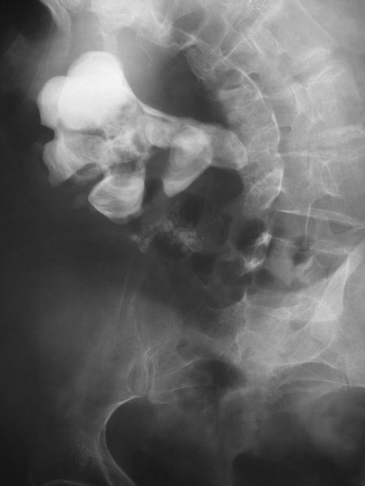

Struvite/Staghorn Stones (~15%)

- Large, moulded to renal pelvis/calyces (“staghorn”)

- Associated with squamous metaplasia

- Often due to chronic infection

- Abdominal X-ray (AXR):

- Detects radio-opaque stones (e.g. calcium)

Nevit Dilmen, CC BY-SA 3.0 <https://creativecommons.org/licenses/by-sa/3.0>, via Wikimedia Commons